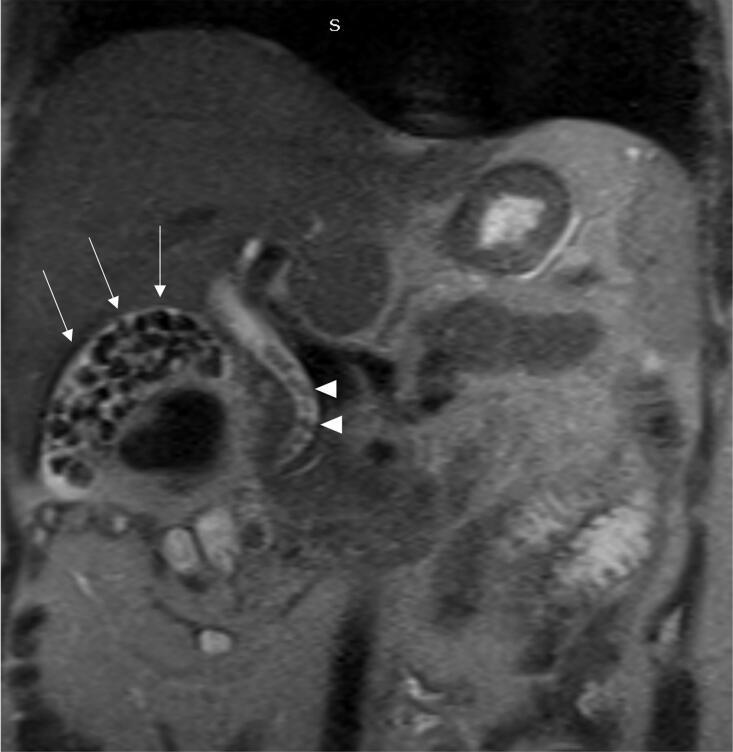

We present a case of a 30-year-old pregnant at 18 weeks of gestation who presented with acute-onset, progressively worsening epigastric pain radiating to the back associated with nausea and bilious vomiting but no fever. Laboratory investigations revealed elevated serum amylase and lipase, consistent with acute biliary pancreatitis, alongside obstructive biochemical features on liver function tests. Imaging confirmed multiple gallstones, choledocholithiasis, and a dilated common bile duct (CBD). She underwent successful ERCP with sphincterotomy and stone extraction followed by laparoscopic cholecystectomy in the same session. The patient had an uneventful recovery and was discharged on postoperative day three without complications.

我们报告一例30岁妊娠18周的孕妇,其表现为急性发作、逐渐加重的上腹部疼痛,放射至背部,伴有恶心和胆汁性呕吐,但无发热。实验室检查显示血清淀粉酶和脂肪酶升高,符合急性胆源性胰腺炎,同时肝功能检查有梗阻性生化特征。影像学检查证实有多个胆结石、胆总管结石及胆总管扩张。她在同一次手术中成功接受了ERCP括约肌切开术和结石取出术,随后进行了腹腔镜胆囊切除术。患者恢复顺利,术后第三天出院,无并发症。